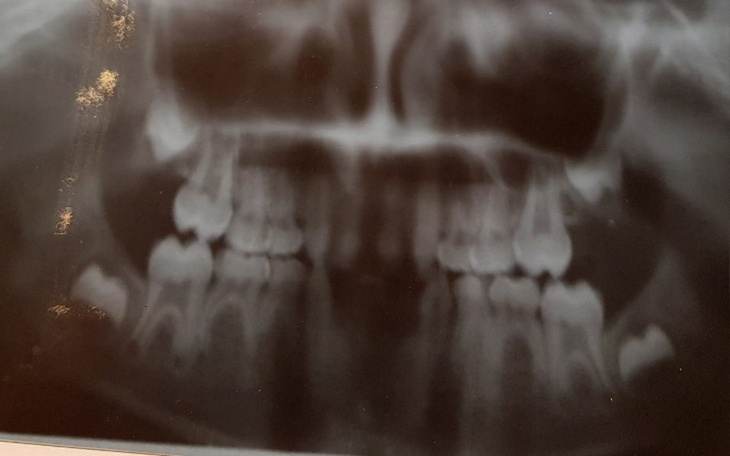

Agenezja zębów oraz oligodoncja jest rzadką wrodzoną wadą rozwojową o podłożu genetycznym, z którą się urodziłem. Z powodu braku zawiązek zębów stałych, zdeformowane zęby mleczne pozostały mi na całe życie. Natomiast część uzębienia nie wyrosła nigdy, nawet jako zęby mleczne.

Zamieszczone zdjęcie RTG przedstawia moje uzębienie, jednak sprzed wielu lat. Zęby mleczne były słabe i bardzo szybko ulegały zniszczeniu. Obecny stan uzębienia jest daleki od tego, co ukazuje zdjęcie.

Zabiegi, które chciałbym móc wykonać, dotyczą ekstrakcji górnych, przednich zdeformowanych zębów mlecznych i wstawienie w ich miejsce mostu protetycznego z koron osadzonego na filarach przygotowanych z własnych zębów trzonowych. Być może wymagane byłyby dodatkowe implanty w 2 punktach, tak aby most utrzymywał się w 2 punkatch z tyłu, oraz w 2 punktach z przodu górnej szczęki.

Dolna szczęka wymaga kompletnego mostu całego uzębienia, opartego na implantach w 4 punktach. Dwa obecne zęby mleczne z przodu dolnej szczęki mogą okazać się zbyt słabe, aby posłużyć za filary dla mostu. Wszystko to musi być jeszcze poprzedzone kilkoma ekstrakcjami chirurgicznymi pozostałości po zębach trzonowych.